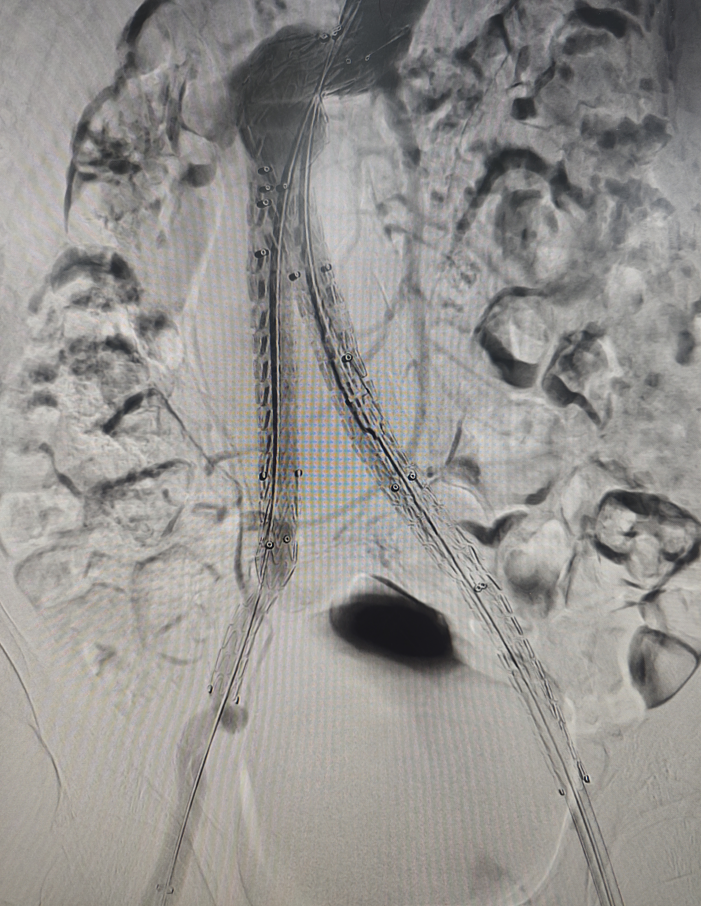

![[7]图片.png [7]图片.png](/upload/202406/12/2024061216340172582.png)

腹主动脉瘤覆膜支架置入术中造影图

6月7日进行了“腹主动脉瘤腔内隔绝术”,分别穿刺右侧肱动脉、双侧股动脉,腹主动脉造影定位双侧肾动脉,考虑扭曲瘤颈构型,采用“壁咚”技术,选择肾下锚定,不干扰肾动脉,使支架充分贴合扭曲的瘤体,能够顺应动脉瘤构型,锚定密封更安全。参考骨性标志,标记腹主动脉主体腹膜支架放置位置,引导主体支架系统至瘤体近端颈部,精准释放。其后依次释放短腿、长腿侧支架,最后造影,确认位置理想,各分支血流通畅,无内漏。